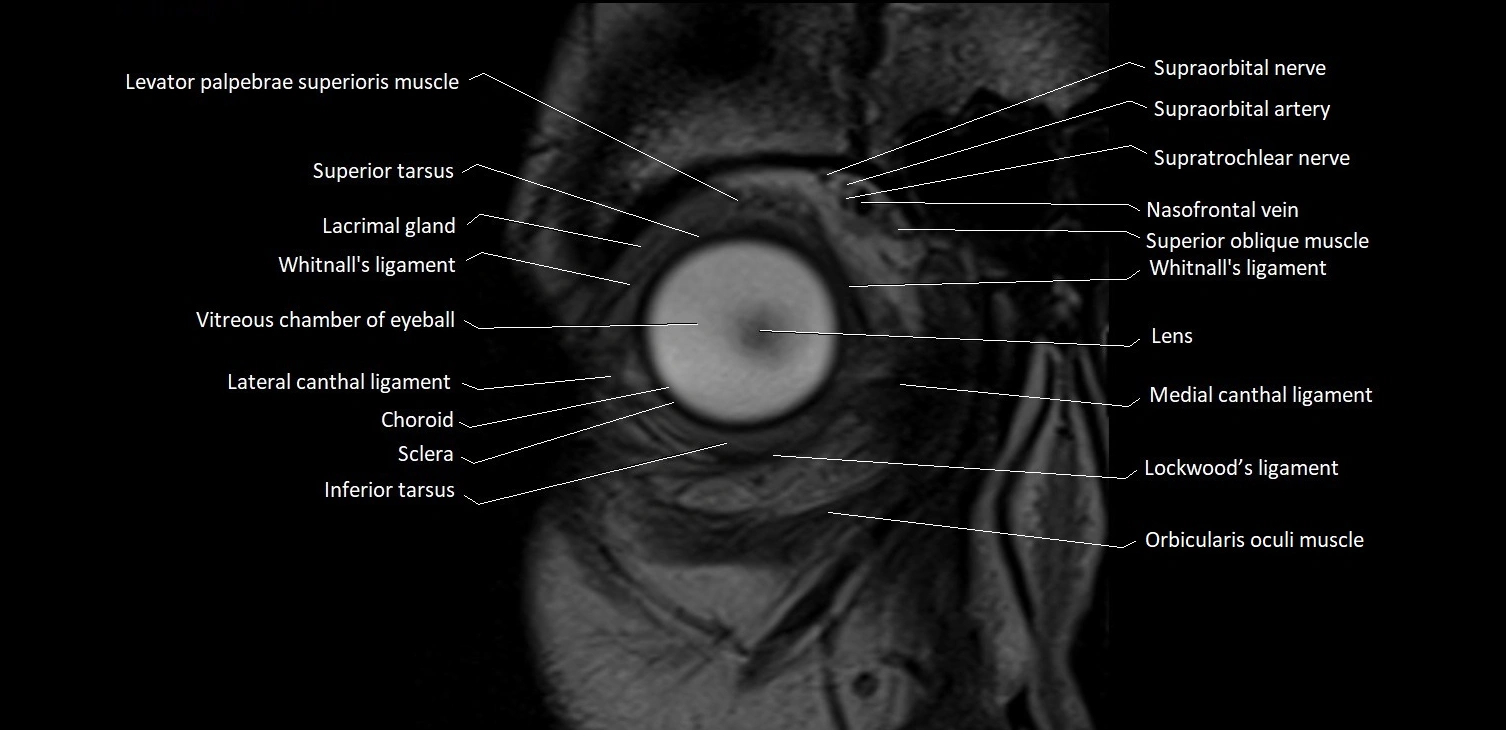

- Abducens nerve (Cranial nerve VI)

- Abducens nerve (orbital part )

MRI images